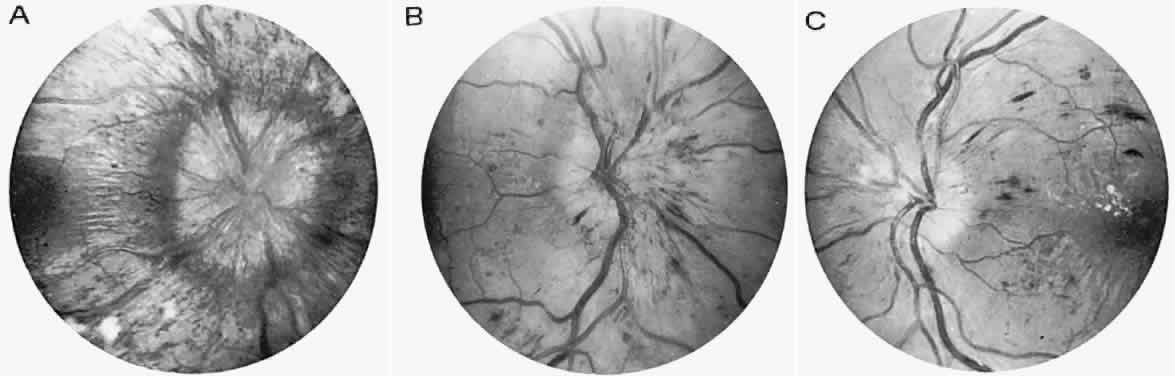

Central field defects with acuity loss occur with photoreceptor degeneration that especially affects the macula, so-called retinitis pigmentosa inversa, but this disorder likely represents a separate nosologic class, the cone-rod dystrophies (see below) (Fig. 3). Severe visual defect in early infancy is frequently enough caused by a primary outer segment retinal abiotrophy, Leber's congenital amaurosis, although this is probably not a single clinical entity. This disorder is characterized by the following: severe impairment of vision, present at birth or becoming evident during early to late infancy; a fundus that may initially approach normal, but within years, optic atrophy, diffuse fine pigmentary degeneration, and attenuation of the arteriolar tree are evident; and either an absent or a markedly reduced ERG response. Other variable features include nystagmus, photophobia, digito-ocular maneuver (forceful eye rubbing with sunken globes; “blindisms”), strabismus, cataracts, hyperopia, mental retardation, deafness, renal anomalies, seizures, hydrocephalus, and focal neurologic deficits (e.g., cerebral diplegia). Hereditary transmission is typically autosomal recessive10 (see Volume 2, Chapter 13).

Fig. 3. Cone-rod dystrophy or so-called “retinitis pigmentosa inversa” in a young man with progressive spinocerebellar degeneration and 20/200 acuity in each eye.

As noted above, the macular (“inversa”) form of abiotrophic pigmentary retinopathy is actually a selective loss of cone function, but rod function also is defective. Indeed, retinal dystrophies accompanying many systemic disorders are typically, but not exclusively, this macular form. Of special neuro-ophthalmologic interest is the association of this and other geographic pigmentary patterns with hereditary cerebellar ataxias,11,12 with olivopontocerebellar and spinocerebellar degenerations,12–14 and with Friedreich's ataxia.15 These disorders are usually dominantly inherited, with variable expression of early life onset of progressive spasticity, ataxia, slowed saccades or supranuclear ophthalmoplegia, and chorioretinal macular dystrophy. Trinucleotide gene expansion (point mutation) is incriminated, but not exclusively. In Friedreich's ataxia, the most common inherited, if clinically inhomogeneous, spinocerebellar ataxia, a mitochondrial location of frataxin (Friedreich's ataxia protein) has been identified; this locus on chromosome 9 reflects the relationship with vitamin E deficiency ataxia and certain neuropathies with mutations in nuclear genes.16

Other subsets of pigmentary retinopathies are due to mitochondrial DNA mutations and are associated with migraine, ataxia, dementia, and Leigh's disease17; the sporadic or maternally inherited MELAS syndrome of mitochondrial myopathy, encephalopathy, lactic acidosis, and stroke-like episodes, usually presents in the teens as cognitive regression, headaches, and cerebral lesions causing field defects.18–20 Even in family members, there is considerable variation of genotypic and phenotypic specificity in metabolic disorders mediated by mitochondrial DNA aberrations, including Kearns-Sayre progressive external ophthalmoplegia (see Volume 2, Chapter 12) and other conglomerations of pigmentary retinopathies. Further identification of gene point mutations will eventually provide a more precise classification.